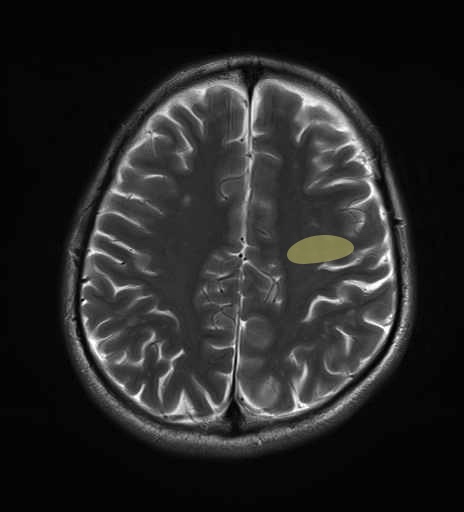

運動系 錐体路系に色を付けました。

■皮質脊髄路(いわゆる錐体路):一次運動野から脊髄遠隔の下位運動ニューロン細胞体まで

■皮質核路:一次運動野から橋及び脊髄神経核まで